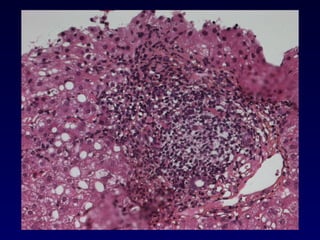

Infiltrat lymphocytaire portal diffus nodulaire caractéristique d’une hépatite chronique. Hépatite chronique - Lésions élémentaires

Destruction de la lame bordante par des cellules inflammatoires Evaluation de l’intensité - Extension: focale ou diffuse (/ espace porte) - Nombre d ’EP atteints La nécrose parcellaire est un marqueur d’activité de l’hépatite chronique Nécrose périportale Piecemeal necrosis Nécrose parcellaire Hépatite d’interface Hépatite chronique - Lésions élémentaires

NP2

NP2 NP2